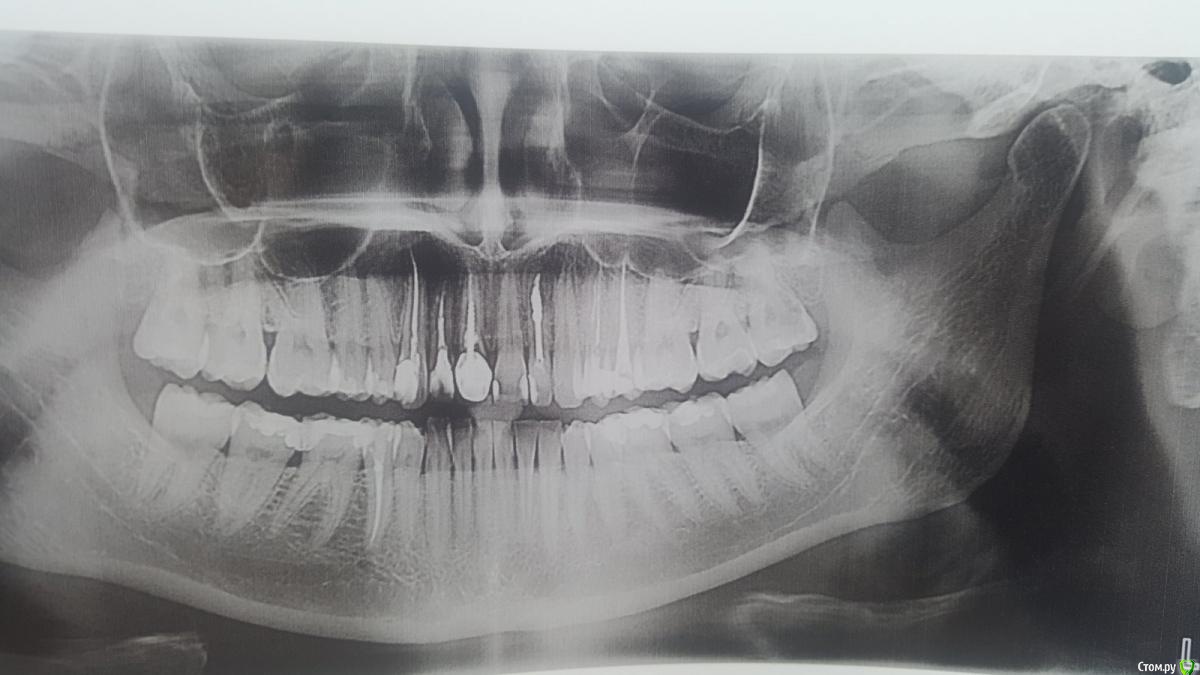

Sergey007 Опубликовано 5 июля, 2020 Поделиться Опубликовано 5 июля, 2020 Здравствуйте, на протяжение 3 месяцев переодически возникает острая боль в верхних зубах(на снимке верх с права если с центра считать 4 и 5). С начала подозревали 4й, удали нерв, через неделю боль вернулась, решили удалить нерв в 5м, после пломбировки канала, боль вернулась в острой форме. Сделали панарамный снимок, Врач сказал что на нем ничего не видно. Хотелось бы узнать альтернативное мнение, снимок прилагаю. Заранее большое спасибо за ваши ответы. Ссылка на комментарий

red_butler Опубликовано 5 июля, 2020 Поделиться Опубликовано 5 июля, 2020 я бы в первую очередь смотрел нижние зубы и зуб мудрости.Опишите как болит? Ссылка на комментарий

Sergey007 Опубликовано 6 июля, 2020 Автор Поделиться Опубликовано 6 июля, 2020 Спасибо огромное за ваш совет, обратили внимание на зуб мудрости и нашли там дыру с нервом. Будим удалять, надеюсь проблема решитса. Ссылка на комментарий